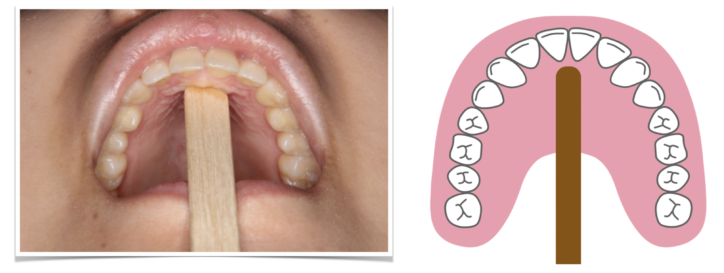

①スティックでスポットを触り、ゆっくり5秒間

②スティックを離し、同じ場所を舌の先で触り、つけたまま5秒間

姿勢を良くして、鏡を見ながら①と②を交互に5〜10回行います。

このとき、舌の先を丸めないで、舌の脇を締め、先を尖らせてください。

①スティックを口の前に利き手で垂直に持つ。

②口を大きく開ける

③舌を引き締め、舌をとがらせるようにまっすぐ前に出す

④舌とスティックの両方で3秒間押し合う。

⑤スティックを離し、口唇を閉じて3秒間力を抜いて舌を休ませる

⑥3〜5を繰り返す

5~10回繰り返します。舌の先を丸めないで行うことと、しっかりと舌の先でスティックを押すように意識することがポイントです!